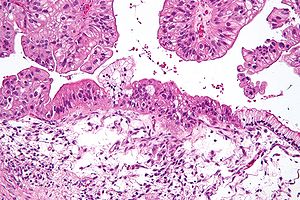

A decades-long study on ovarian cancer has produced disappointing results, says a British researcher. Following more than 200,000 women for an average of 16 years, the randomized trial found that annual screening for the cancer did not ultimately reduce the number of deaths from the disease. The results were published this week in the journal The Lancet. “Our aim was to try and establish a screening programme for ovarian cancer like we have for cervical and breast cancer,” said Usha Menon, lead investigator of the UK Collaborative Trial of Ovarian Cancer Screening (UKCTOCS) and a professor of gynecological cancer at University College London.